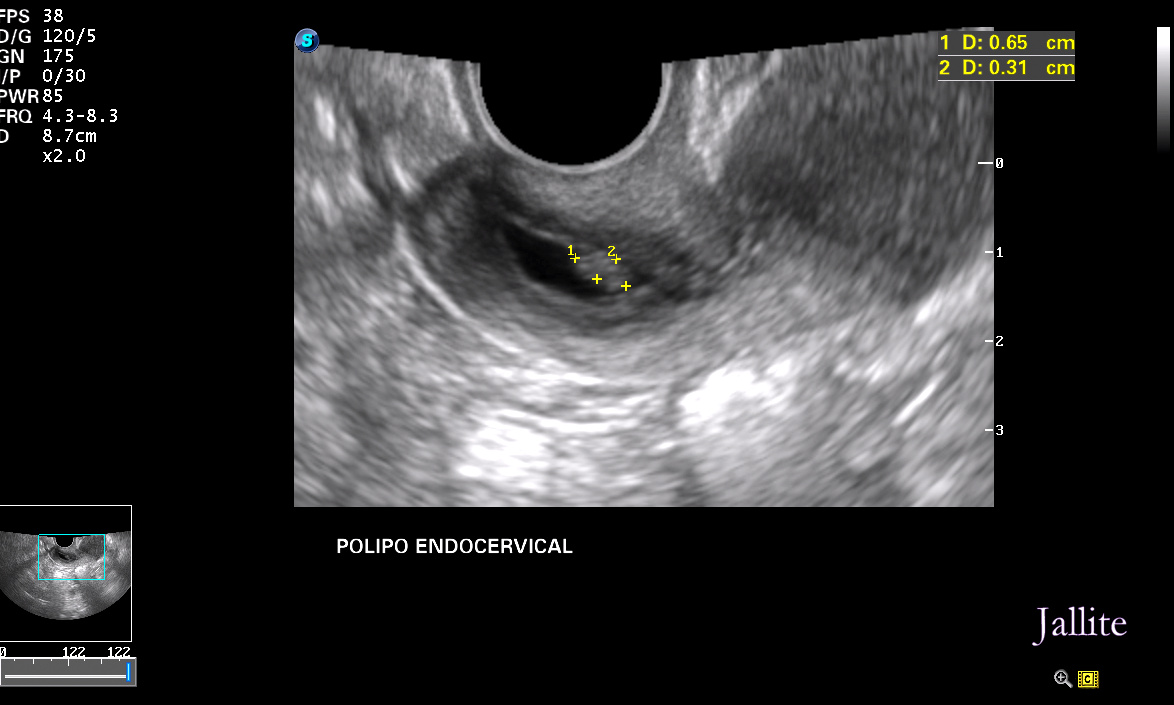

O Que Significa Pólipo Endocervical? Quando falamos em "pólipo endocervical", estamos nos referindo a esses crescimentos específicos que ocorrem no colo do útero. Geralmente, eles são benignos, mas, em alguns casos, podem se tornar malignos, o que é motivo de preocupação. Vamos discutir mais sobre esse aspecto posteriormente neste.. Há dois tipos deles: pólipo endometrial e pólipo endocervical. Neste artigo iremos explicar quais são suas características e a diferença entre eles. Os pólipos endometriais são, como o próprio nome sugere, as lesões que desenvolvem-se no endométrio e, portanto, localizam-se na cavidade uterina. Eles são constituídos a partir do.